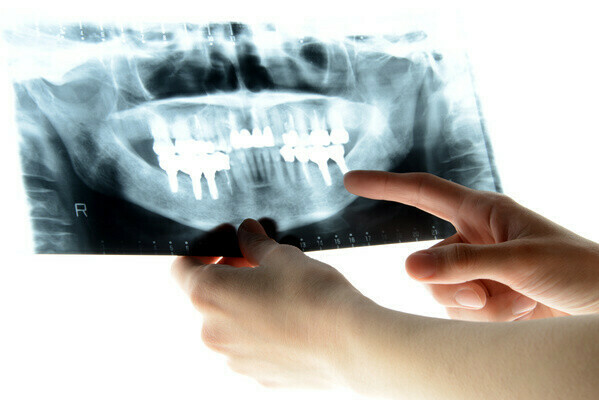

2026/01/01歯科の「クラウン」と「インレー」とは

「クラウン」や「インレー」という言葉を聞いたことがある方は多いと思いますが、それぞれの特徴や違いなどを知っている方は多くないはずです。 このブログ記事では、クラウンとインレーの特徴やメリット・デメリットなどをご紹介します。

クラウンは、歯茎から出ている部分の歯全体(歯冠)を覆う被せ物のことです。虫歯が進行して歯が大きく損傷している場合や、神経の治療をした場合などに使用されます。歯冠全体を覆って強度を保つため、歯を削る量が多くなるのが特徴です。前歯から奥歯まで幅広く使われています。

保険診療で使用されるクラウンは「前装冠」「FMC(フルメタルクラウン)」「CAD/CAM冠」などがあります。 自費診療では「セラミッククラウン」「メタルボンド」「ゴールドクラウン」「ジルコニアクラウン」などが使われています。

インレーは、比較的小さな奥歯の虫歯や歯と歯の間などに使われる詰め物です。食事の際に強い力が加わる部位には、強度の高い素材が使用されます。

小さな虫歯にはCR(コンポジットレジン)が使用されることがありますが、インレーより強度が低いため、強い力がかかる部位には向きません。 保険診療で使用されるインレーはメタルインレーのみで、自費診療では「セラミックインレー」「ジルコニアインレー」「ゴールドインレー」などがあります。

クラウンもインレーも、虫歯などで失った歯の機能や形を回復させるために使用されます。失った範囲が狭い場合にはインレー、広い場合にはクラウンが使われることが一般的です。

クラウンはインレーより強度が高い一方で、歯冠を覆うため削る量が多くなります。材料が同じ場合、削る量が少ないインレーのほうが費用が安いことが多いです。

クラウン・インレーともに保険診療と自費診療があり、自費診療のものは審美性や強度に優れていることが特徴です。どちらを使用するかは、欠損の大きさや歯の場所、患者さんの希望を踏まえて歯科医師が判断します。